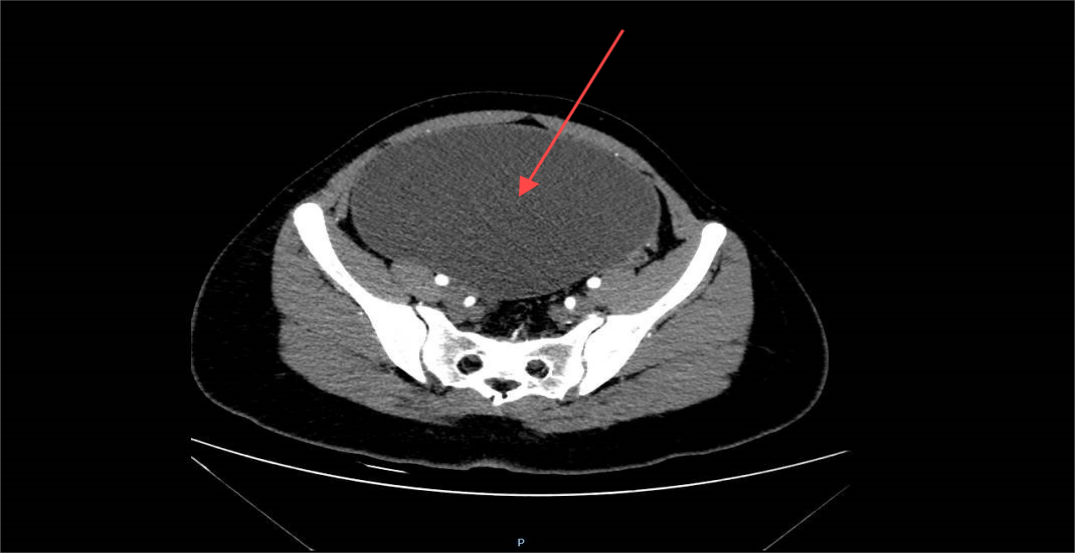

盆腹腔肿物的CT影像